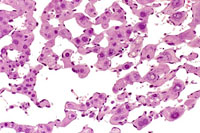

This hemangiosarcoma is well demarcated from the normal hepatic parenchyma; sharp demarcation is an unusual feature of hemangiosarcomas. Large blood-filled lakes are apparent. Higher magnification shows bands of spindle-shaped endothelial cells with attendant destruction of hepatocytes, proliferation of plump endothelial cells, and atrophy of hepatocytes.